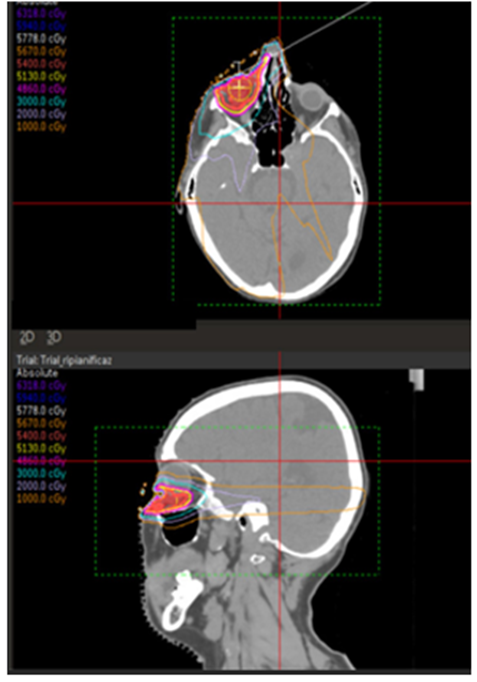

A Gross Target Volume (GTV) was delineated, then it was expanded 2 mm to Clinical Target Volume (CTV) and other 3 mm to Planning Target Volume (PTV). The prescribed dose was 54 Gy delivered in 27 fractions, at conventional fractionation [8] The locoregional Organs at Risk (OARs) were identified.

The treatment planning was performed with Philips Pinnacle3 Evolution V16.4.3 treatment planning system (TPS), with double arcs Volumetric Arc Technique (VMAT) and 6 MV photons (Figure.3).

Figure 3: Treatment plan